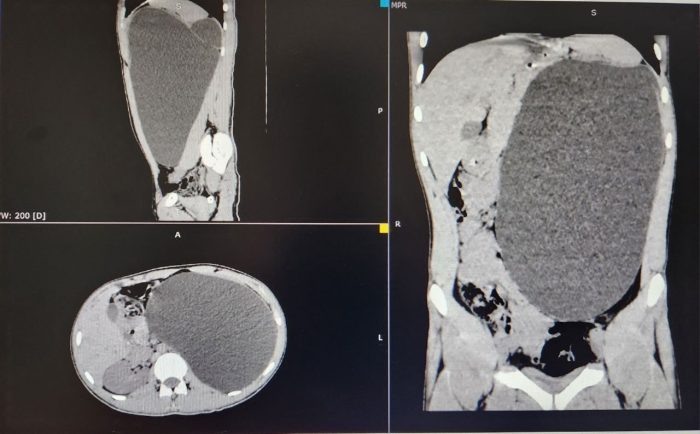

Юный новосибирец пришел на обычный медосмотр для трудоустройства и лишился почки. Оказалось, что орган достиг «размера 5-литровой бутылки», на его месте был гигантский пузырь, заполонивший весь живот и грозивший лопнуть в любой момент. Самым поразительным оказалось то, что парень вообще не испытывал дискомфорта и не подозревал об опасности. Неизвестно, чем был закончилась эта история, если бы не обычный профосмотр. 17-летний юноша пришел на него как на очередную формальность при трудоустройстве, а его внезапно отправили в стационар Детской городской клинической больницы №1. В кабинете УЗИ было сделано неожиданное и тревожное заключение: «Объемное образование, размер невозможно измерить, левой почки нет». «Такое бывает либо при огромных опухолях, либо при гидронефрозе IV степени, когда почка превращается в гигантский мешок, заполненный мочой. У пациента был второй вариант. Почка достигла размеров пятилитровой бутылки! Она занимала почти весь объем живота и давила на все соседние органы.

Фото ДГКБ №1.

«Такое бывает либо при огромных опухолях, либо при гидронефрозе IV степени, когда почка превращается в гигантский мешок, заполненный мочой. У пациента был второй вариант. Почка достигла размеров пятилитровой бутылки! Она занимала почти весь объем живота и давила на все соседние органы. Это была настоящая «бомба замедленного действия»: любая травма, случайный удар в живот — и мешок мог разорваться внутри», — рассказали сегодня в ДГКБ №1.

Такому результату медосмотра были удивлены все. Ведь молодой человека ни на что не жаловался, состояние его почки не вызывало никаких побочек. Родители сначала даже не поверили и усомнились в необходимости операции. Но после разъяснений врачей согласились. Юноше провели лапароскопию. Через четыре небольших прокола откачали всю жидкость, а затем «ювелирно» отделили капсулу от тканей и наложили клипсы на сосуды. Фактически хирурги «достали пятилитровую бутылку через замочную скважину».